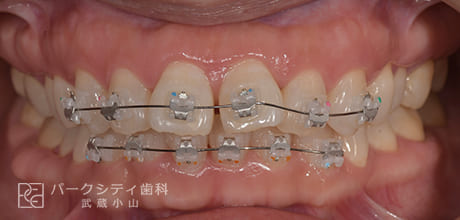

CASE.02

表側の部分矯正の症例

術前

術中1か月

術中3か月

4か月

- 主訴

- 前歯の隙間が気になる

- 治療法

- 表側の部分矯正

- 治療期間

- 4か月

- 費用

- ¥413,600

【内訳】

検査料:¥33,000

装置料:¥165,000×2(上下)

チェック:¥4,400×4

保定装置:¥16,500×2(上下)

上下表側に装置をつけ、隙間を閉じながら歯並びを整えて、約4か月で保定へ移行しました。